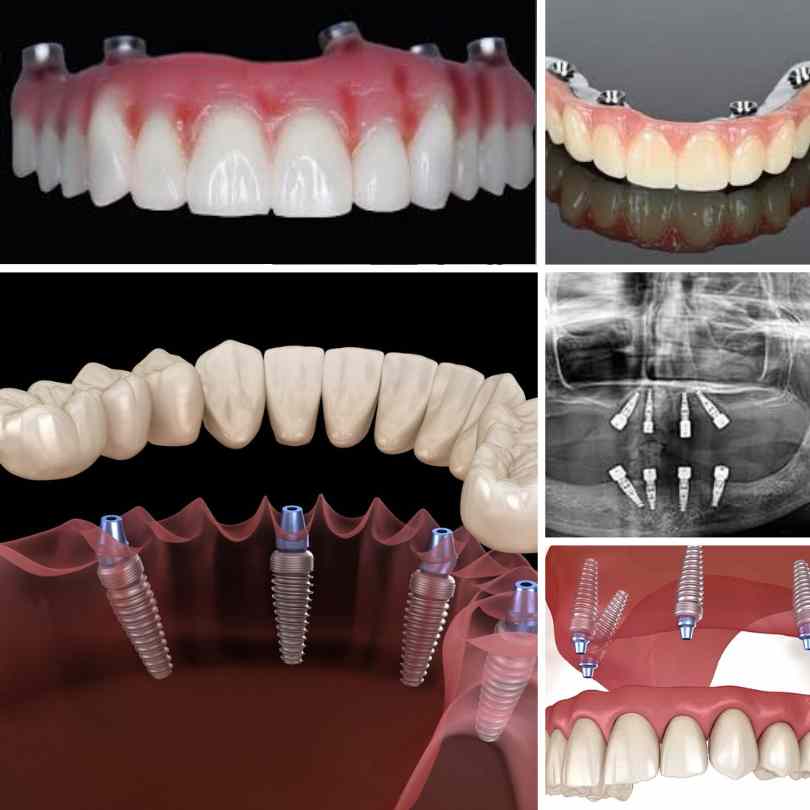

Sistemul All on 4/6 îți reface complet dantura

Protezele dentare pe implanturi sunt în mod clar metoda preferată astăzi pentru înlocuirea dinților. Această înlocuire completă a dinților este o procedură specializată de implant dentar, în care, cu doar patru implanturi, medicii stomatologi din Clinica ClassMed pot înlocui un întreg arc de dinți, eliminând necesitatea a zeci de implanturi individuale.

Procedura de implant dentar All-on-4/6 este mai puțin invazivă, astfel încât chirurgia în sine este mai scurtă decât procedurile de implant din trecut.

În doar o zi îți poți schimba viața. Așa este, All-on-4/6 se realizează într-o singură zi – intri cu zâmbetul tău vechi și pleci în aceeași zi cu un zâmbet nou perfect – Dinți în 24 - 48 de ore - datorită protezei dentare provizorii.